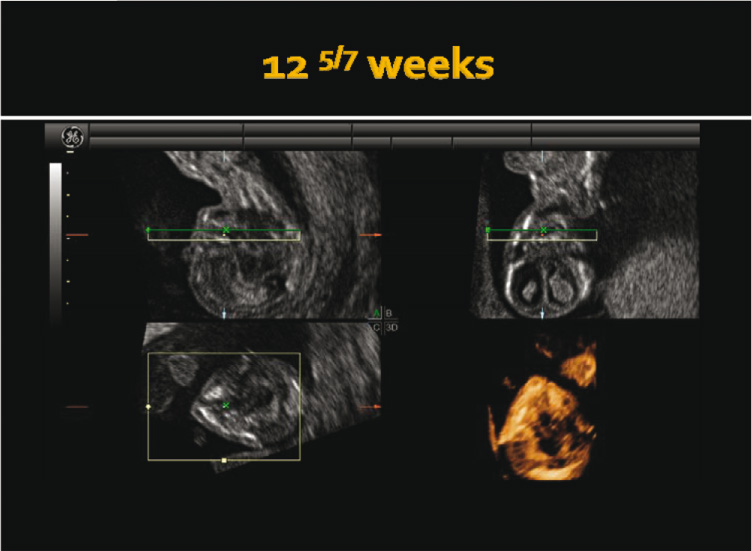

A 36-year-old primigravida was referred to the New York University ultrasound unit for nuchal translucency (NT) screening at 12 weeks and 5 days’ gestation. The NT measured 1.7 mm, while the serum screen was normal. An early anatomical survey at the time of the first-trimester screen revealed unilateral left cleft lip and palate (Figure 1). Subsequently, a transvaginal 3D scan was performed using a GE E8 ultrasound machine with a 5–9 transvaginal transducer (General Electric Medical Division, Milwaukee, WI, USA), which further confirmed the diagnosis (Figure 2). No other anomalies were found during this anatomy survey. Subsequently, ultrasound at 21 weeks’ gestation showed the same anomaly detected during the first-trimester anomaly screening (Figure 3). Prenatal consultation with an orofacial surgeon was obtained at 22 weeks’ gestation. The pregnancy remained otherwise uncomplicated, and delivery was at term as planned. Delivery was attended by the “cleft team” for postnatal management.

First-trimester anatomy survey during NT screening showing unilateral cleft lip and palate at 12 weeks and 5 days’ gestation.